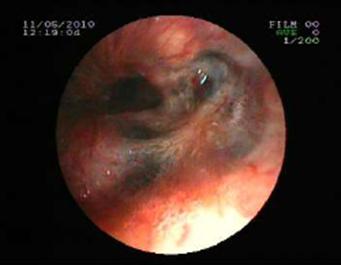

The posterior anterior chest graphy showed consolidation area in right paracardiac region. The high resolution thorax spiral computed tomography (HRCT) obtained on admission revealed consolidation area and atelectasis in right middle lobe (Figure 1). Flexible bronchoscopy (FOB) application was planned to the patient. FOB examination revealed hypervascularisation, hyperemia, deformed bronchial trees and these findings were similar to previous FOB findings. Previous FOB examination has been done to examine middle lobe atelectasis. However, white necrotic lesions were observed in orifice of the middle lobe and at entry of main right bronchus and intermediate bronchus differently from previous bronchoscopic examination (Figure 2, 4). Biopsy from necrotic lesions and bronchus lavage were performed. Histological and cytological findings of material were benign. Microscopic findings of biopsy revealed infection that consists of concentrated lymphoplasmocytes, regular cartilage, and a few polymorph nuclear leucocytes. No AFB was performed on the biopsy specimen. AFB was negative in bronchus lavage; however, mycobacterial cultivation was positive revealing mycobacterium tuberculosis and sensitive to all major tuberculosis agents.

Figure 4

White colored necrosis area in distal trachea and entry of right main bronchus

Tuberculosis treatment was initiated with isoniazid with a daily dose of 300 mg, rifampicin 600 mg, ethambutol 1500 mg, pyrazinamide1500 mg and these doses were planned to be continued for further 6 months. Clinical remission started after two weeks of the treatment period. Control sputum samples were obtained and control culture analysis was performed at the end of two months therapy. Both of these were negative for AFB. We observed significant clinical and radiological remission at the end of three months of this treatment period. Control FOB examination performed in the sixth month of the therapy demonstrated that the white colored necrotic lesions disappeared completely and significant improvement was observed (Figure 3 and Figure 5, respectively).

Figure 5

Necrotic lesions were disappeared at the end of six months treatment